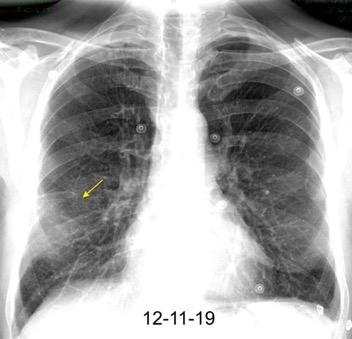

Neumonía a neumococos base izda. con derrame que aumenta.

Broncograma en lateral y en US.

(36-66% en ingresados)